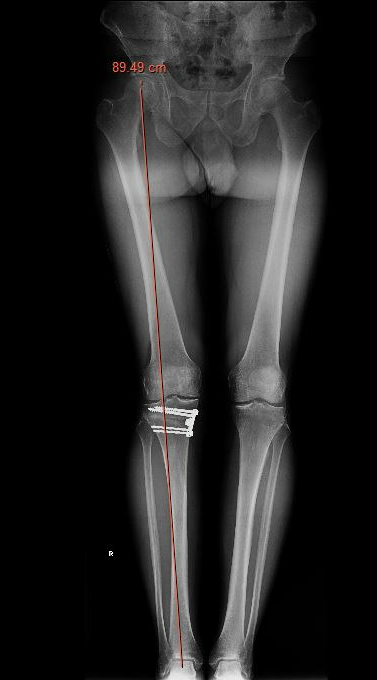

Check correct alignment with drop rod

- goal lateral tibial spine

- Fujisawa point / 62% of the tibial plateau / lateral tibial spine